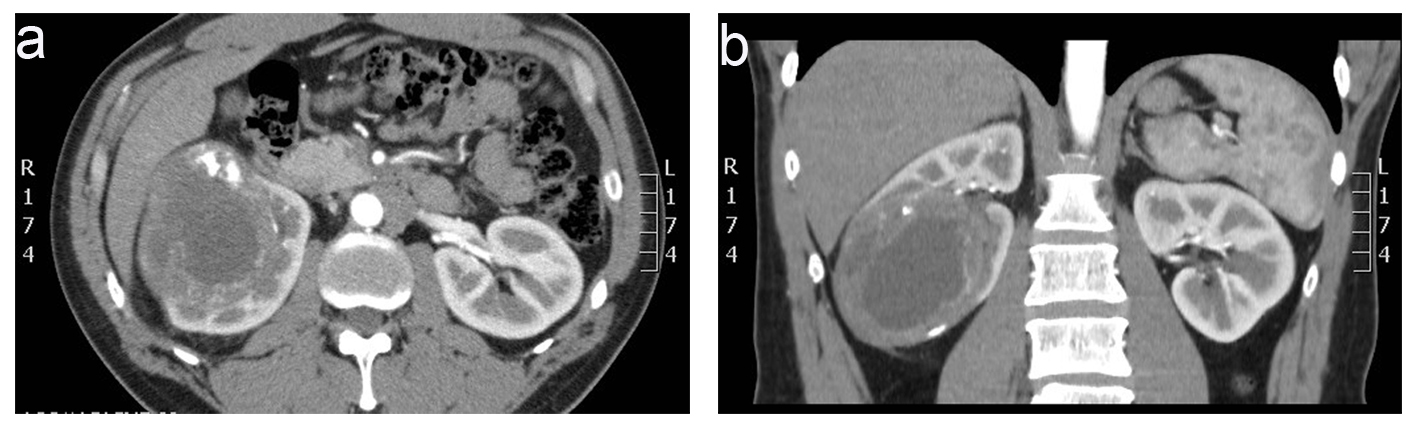

A 46-year-old man presented to our facility for a second opinion regarding the management of his right renal mass shown in ultrasound and computed tomography (CT) of abdomen and pelvis 10 days prior to his visit. CT scan revealed an enhancing, heterogeneous, 9.5 cm endophytic right renal mass (Fig. 1). He had microscopic hematuria on urinalysis and suffered from right flank pain of 1 month duration.

![]() Click for large image | Figure 1. Computed tomography of abdomen and pelvis without contrast prior to surgery showed an enhancing, heterogeneous, 9.5 cm endophytic right renal mass with mild retroperitoneal lymphadenopathy (a) axial view (b) coronal view. |